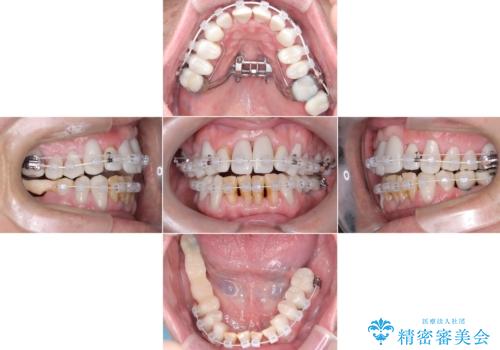

- 強い酸によって歯が広範囲にわたって侵食され、「歯がボロボロになった」と主訴に来院されました。詳細な診査の結果、重度の酸蝕症と診断。失われた歯質や咬み合わせの崩壊が著しいことから、単一の治療では対応が困難と判断し、矯正治療、インプラント治療、セラミック治療を組み合わせた総合的な治療計画を立案しました。矯正治療後に最終的にセラミックを用いて機能性と審美性を回復。患者様と綿密な話し合いを重ね、長期的な口腔内の健康維持を見据えた最適な治療を行いました。

酸蝕症の原因に関しては、医科のほうで解決済みでしたので、失われた機能、審美性の回復のため矯正治療によって歯並びと咬み合わせのバランスを整えセラミックによる修復を行ました。

保存できないと判断した歯は抜歯しインプラントにて治療をおこなっています。

矯正後、歯肉の形態不良のため、歯周外科を行い連続性を獲得しています。